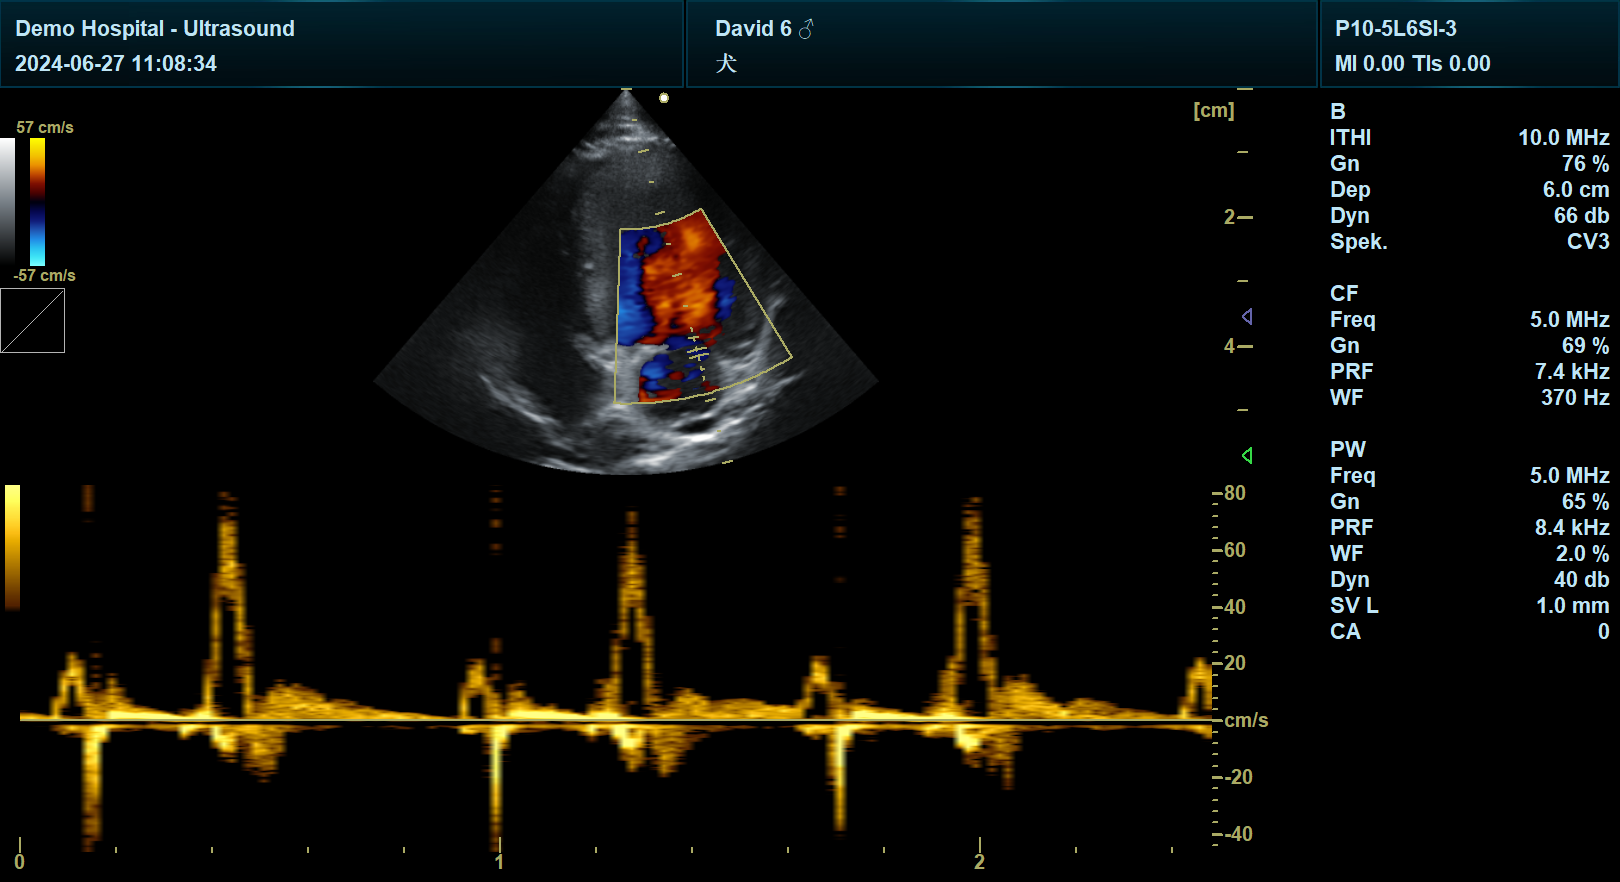

犬左侧胸骨旁长轴右心耳切面的超声扫查,并非标准规范切面,临床中通常需结合左侧胸骨旁长轴面等基础切面,通过调整探头角度和位置来间接观察右心耳区域,具体操作需依据动物个体差异和心脏结构特点灵活调整。

观察目标:通过调整角度,使右心耳区域进入声束范围,结合二维图像识别右心耳轮廓及与右心房的连接关系。

形态异常:右心耳扩张可能提示三尖瓣反流、右心衰竭或心包积液。

血栓形成:右心耳内血栓是犬猫心源性栓塞的常见来源,需重点观察。

三尖瓣疾病:通过观察右心耳与右心房的连接关系,评估三尖瓣反流程度。